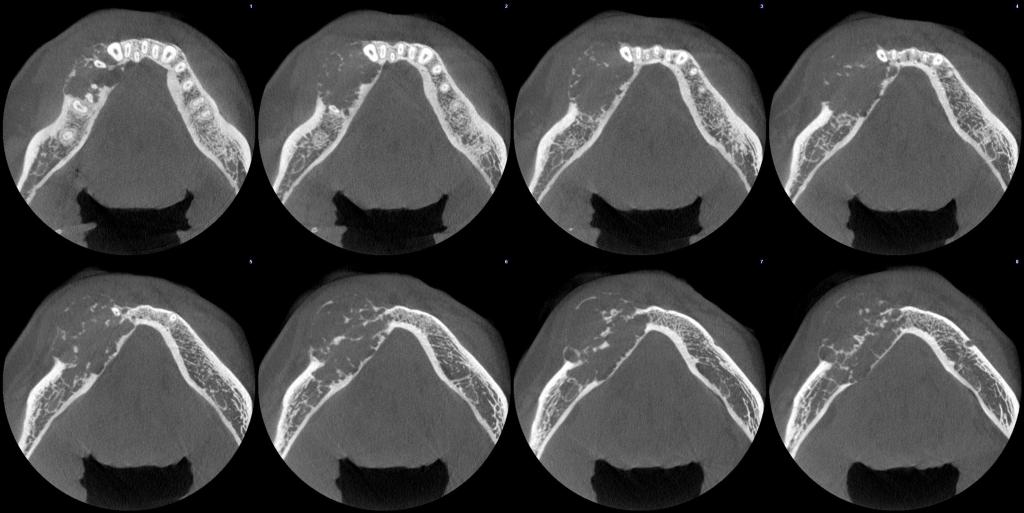

颅颌面CBCT

诊断范围涉及牙体牙髓病、牙周病、阻生牙/多生牙定位、种植牙术前CT评估分析、颞下颌关节CT诊断分析、,颌骨及涎腺疾病、颌面发育畸形、正畸治疗辅助诊断等大部分颌面部疾病,为临床医疗提供强有力的支持。